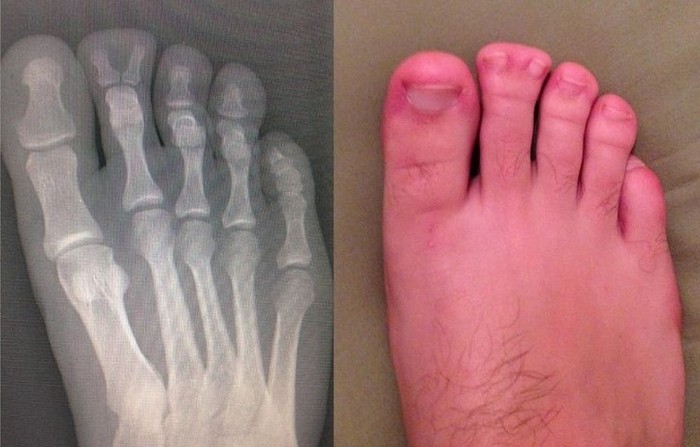

Coba perhatikan bagian telunjuk kakinya. (Foto: Brightside)